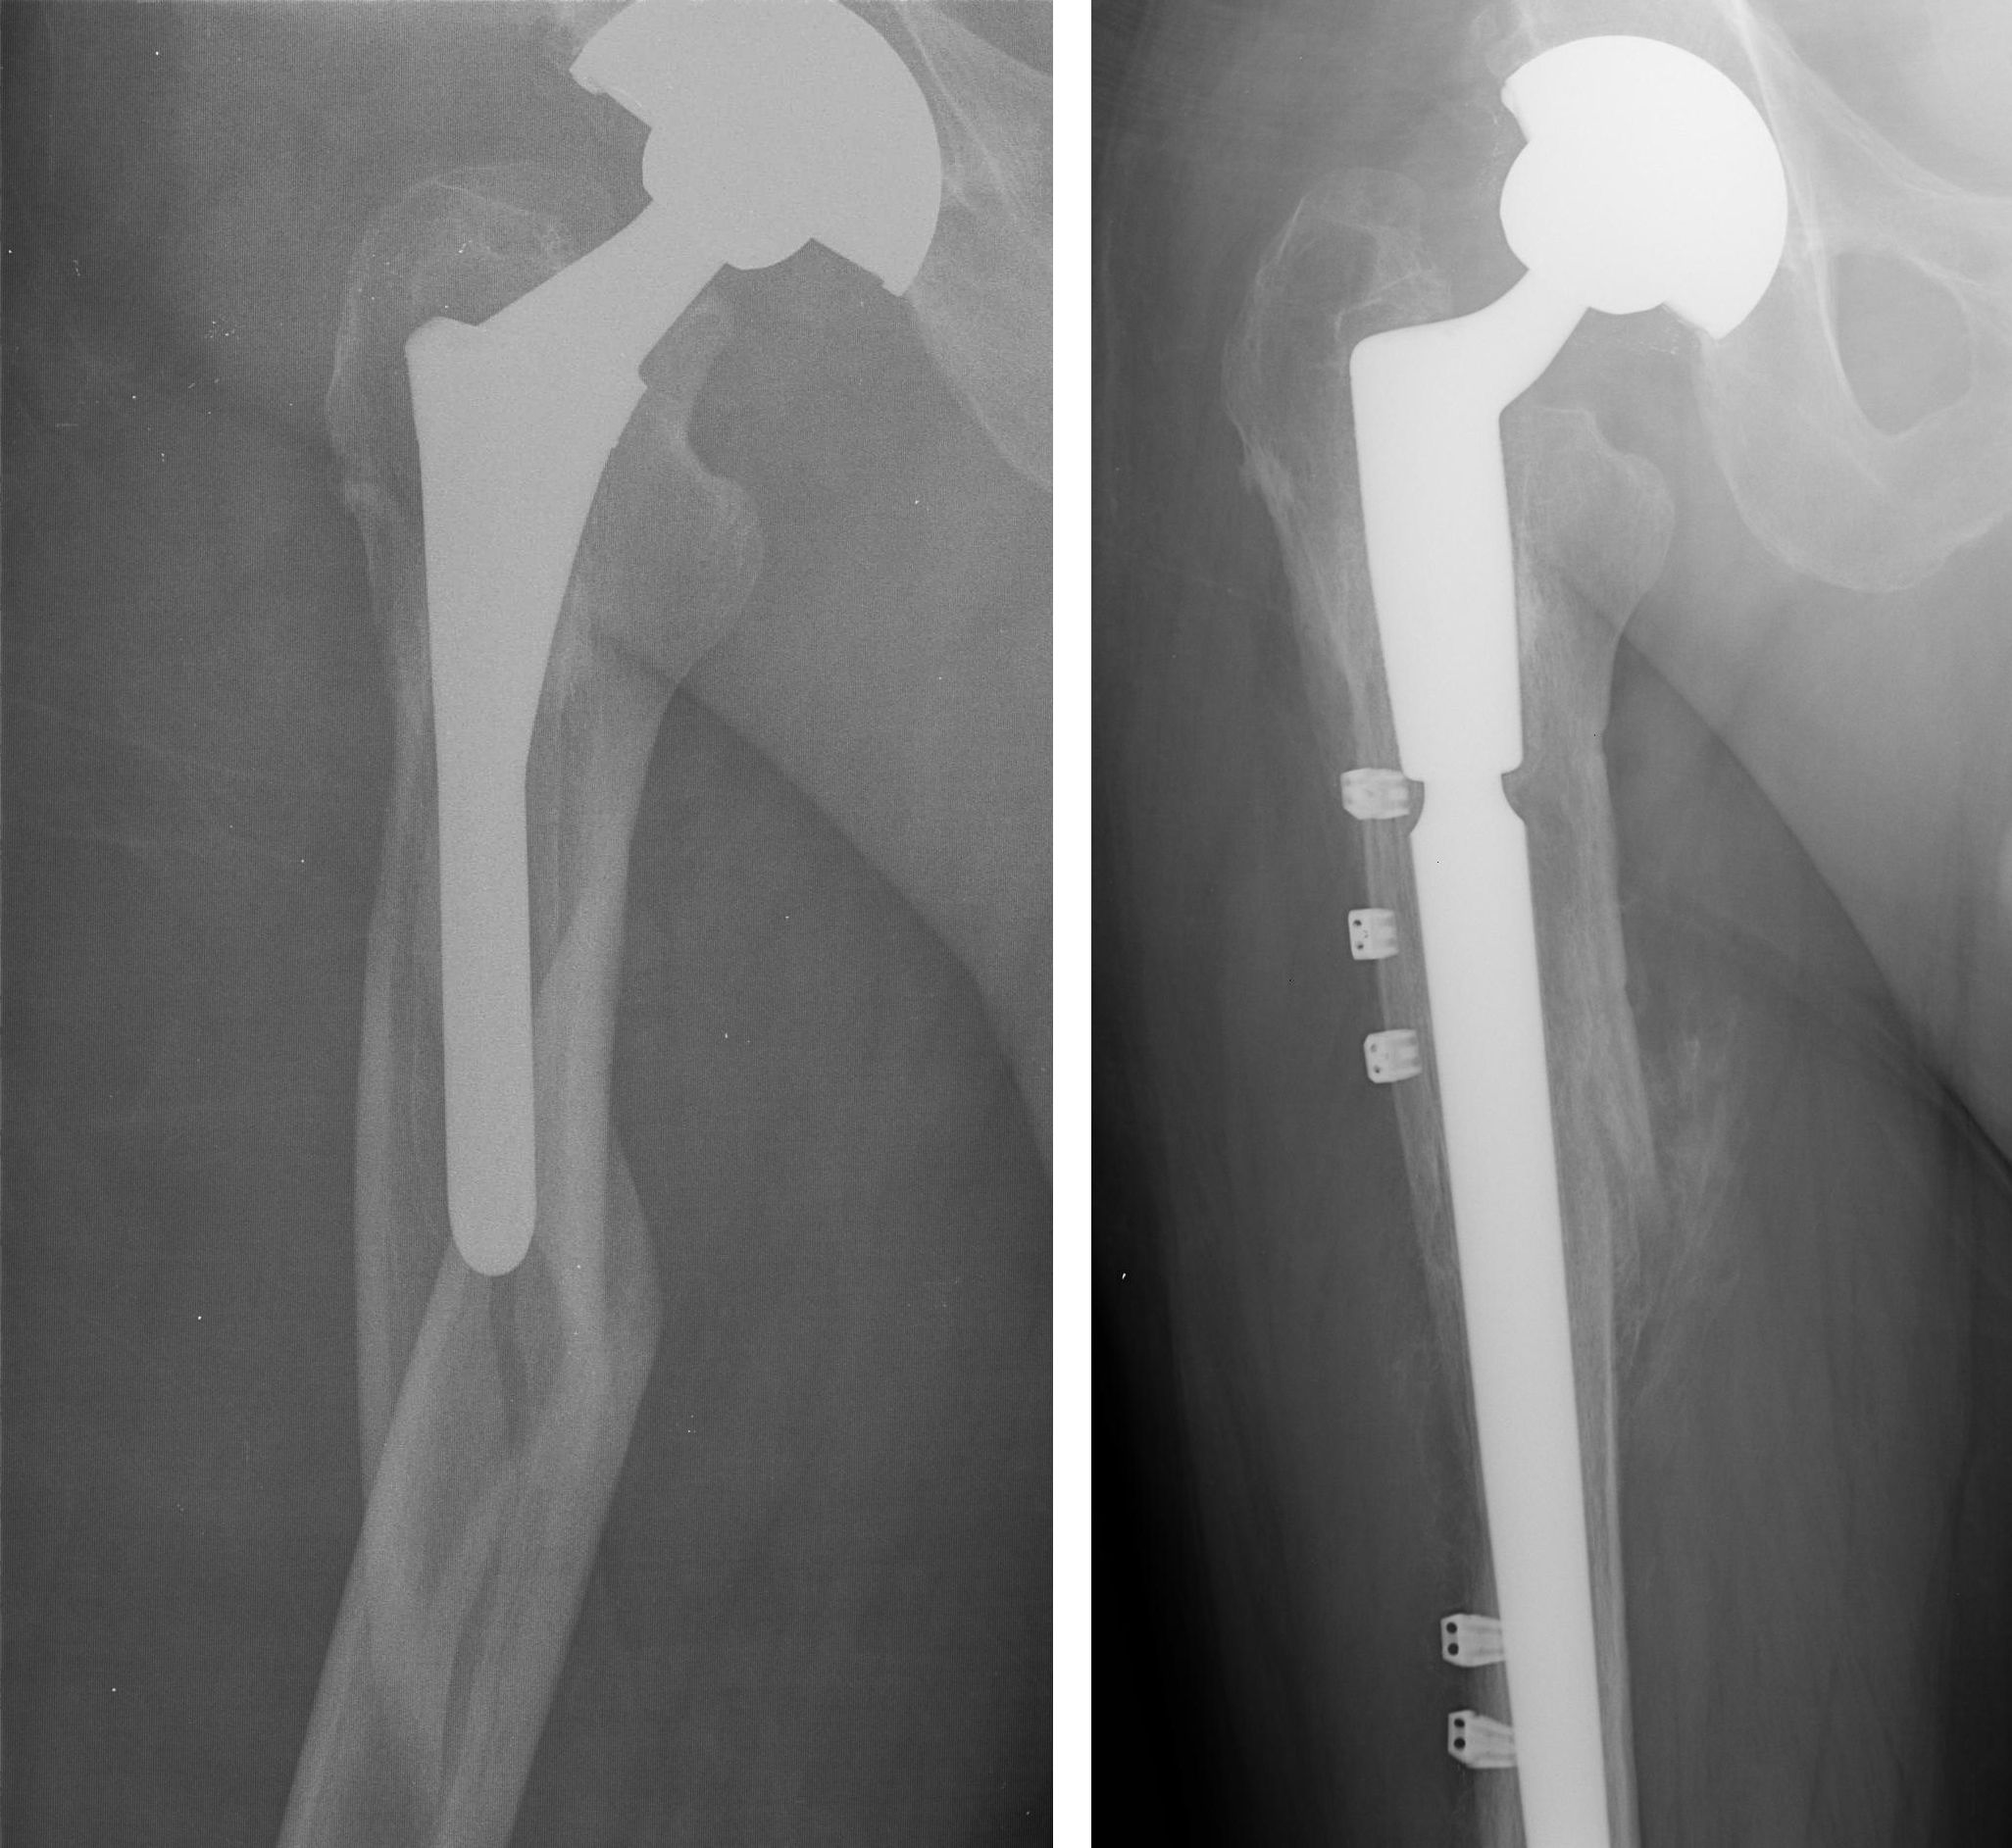

Fracture After Total Hip Replacement OrthoInfo AAOS

From orthoinfo.aaos.org

Fracture After Total Hip Replacement OrthoInfo AAOS Hip Replacement Dislocation Treatment Dislocation after hip replacement is uncommon. In total hip replacement surgery, the whole hip joint can be. A loosening hip replacement implant can be painful. Hopefully you’ll never need to be treated for a hip dislocation after a replacement procedure, but it’s a reality for a number of people. Mild and recurring hip subluxation can be treated by the patient. Hip Replacement Dislocation Treatment.

From orthoinfo.org

Revision Total Hip Replacement OrthoInfo AAOS Hip Replacement Dislocation Treatment But if you have a replacement hip, it may have dislocated more easily, from something as simple as sitting on a low chair or crossing your legs. Understanding which movements cause dislocation after hip replacement is critical. Hopefully you’ll never need to be treated for a hip dislocation after a replacement procedure, but it’s a reality for a number of. Hip Replacement Dislocation Treatment.